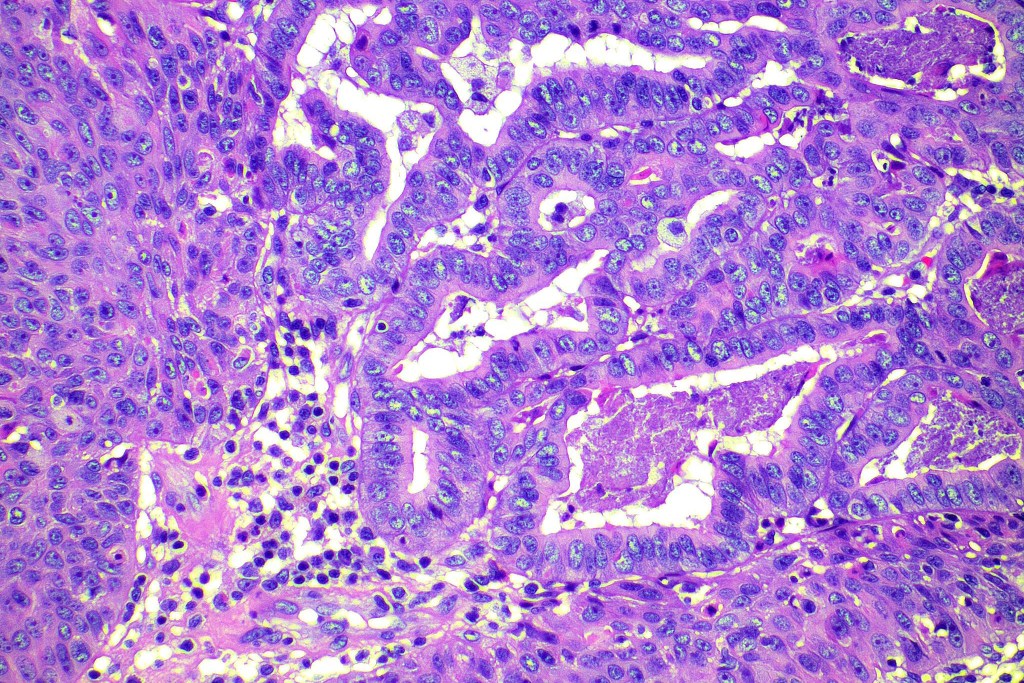

•Biphasic tumor combining squamous cell carcinoma and adenocarcinoma; the latter showing ductal and glandular differentiation

•Glands are lined by cuboidal to columnar epithelium

•Intracytoplasmic lumina sometimes evident

•Glandular foci show mucin

For comparison an actholytic squamous cell carcinoma- in cases of doubt, IHC and special stains for mucin will resolve the problem.